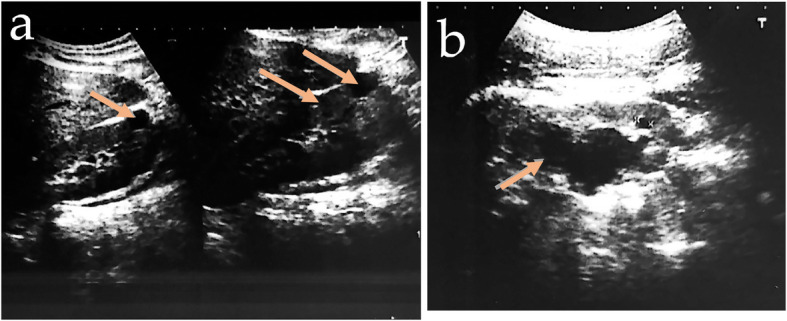

After three years of follow-up after initial diagnosis, blood glucose control was found to be within acceptable levels following a diet with carbohydrate counting and frequently performed physical activity. Her weight is 45 kg, with a body mass index of 17.5 kg/m2. During follow-up, serum calcium and parathyroid hormone levels were normal, and a low 24-h urine calcium (16.3 mg) was identified. A fasting plasma glucose of 118 mg/dL, A1C of 6.2%, total cholesterol of 221 mg/dL, HDL of 85 mg/dL, triglycerides of 230 mg/dL, uric acid of 6.45 mg/dL, and serum magnesium of 1.28 mg/dL was reported. The liver and renal function was, normal but enalapril was prescribed because of a positive microalbuminuria of 273 mg/g. Faecal elastase was 133 μg/g (reference value > 200 μg/g), so pancreatic enzyme supplements were initiated. Total abdominal ultrasound follow-up showed a reduce pancreas body, a right subcapsular simple renal cyst and left diminished corticomedullary differentiation with caliectasis (see Fig. 2).

Fig. 2.

Ultrasonography showing simple renal cysts, diminished corticomedullary differentiation (a) and caliectasis (b). With the arrow are indicated the different phenotypes changes